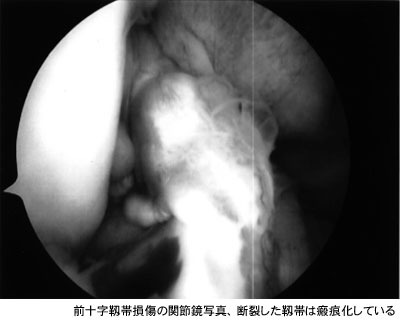

- 前十字靱帯断裂と、半月板も内側の方が損傷という診断をされました・・・

昨日、MRI検査で、前十字靱帯断裂と、半月板も内側の方が損傷という診断をされました。 8年前スキーで転倒した話をしたところ、多分その時でしょう、ということです。5年前からエアロビクスを始め、4年前に一度膝崩れをおこし、水がたまって、抜いてもらったところ、一筋くらいの血が混じっておりました。8年前も4年前もレントゲンのみの検査しかしておりませんので、今回初めて断裂を知りました。4年前のケガ以降、昨秋までエアロビクスを続けておりましたが、特に異常はありませんでした。昨秋、2回続けて膝崩れをおこしたので、ここ3ヶ月あまりはエアロビクスを休んでいます。痛みは膝崩れの後、程なくとれ、腫れは最初からありません。現在は膝に多少の不安定感を感じる程度です。ただ、1月末に早足で歩いている時、膝のつっぱりを感じ、2日間ほど痛みました。日常生活の中では、その1回だけですが・・・。